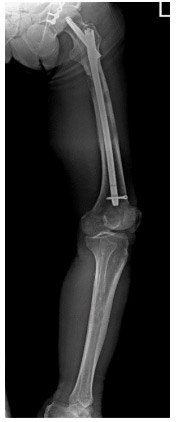

Post-surgery: X-ray shows bone cement and titanium plate in the left acetabulum, and fixation with nails in both thighs.